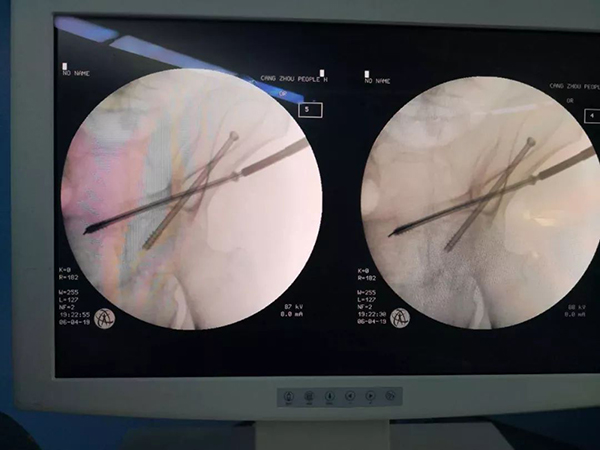

手术前规划

手术后与规划完全吻合

据沧州市人民医院医专肿瘤院区骨科主任刘树江介绍,“天玑”骨科手术机器人可实现更加个性化的手术方案设计和模拟,提供超越人手极限的手术定位精度,可以使患者的软组织损伤小、手术切口小、出血量少、安全性高,患者恢复快。减少了人工操作过程中可能造成的脊髓、血管损伤风险。不需要反复透视来确定进钉位置,医生与患者受到的辐射伤害大大降低,也降低了患者感染的风险。尤其对于上颈椎疾病、脊柱畸形、脊柱翻修、骨盆及髋臼等常规手术难以置钉的患者,以及一些因骨质疏松而不便进行多次进钉尝试的患者极为有利。